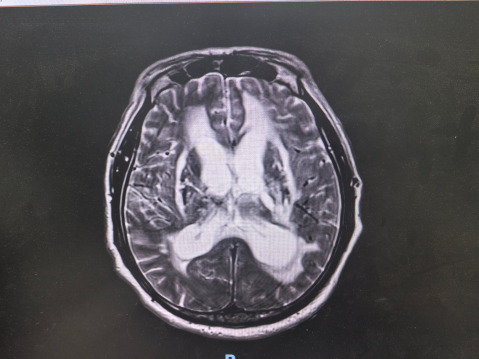

正常压力脑积水需经多维度诊断:医生结合“三联征”症状,通过头颅CT/MRI看脑室是否扩大,再用腰穿放液试验确认脑脊液情况。